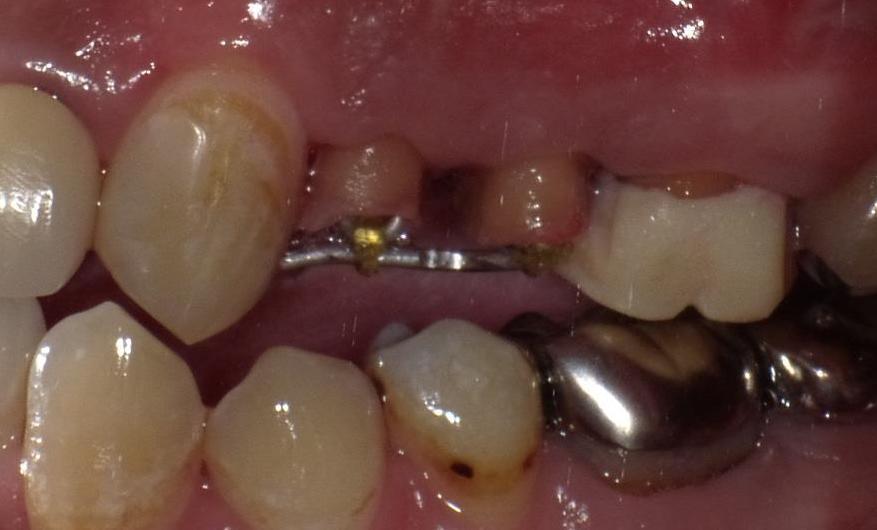

歯ぐきの下に及んだむし歯に対する症例

↓